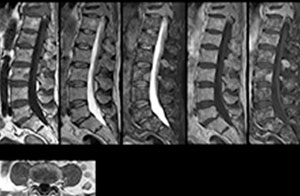

“We use mDIXON TSE extensively in our spine imaging in the emergency room,” says Dr. Karis. “It’s particularly nice in that it is very robust with regard to susceptibility type of problems that would come up with traditional spectral fat-saturated images; these problems are essentially eliminated with the mDIXON technique. In our ED environment it’s really nice to have the fat-free imaging that goes along with the mDIXON technique.

“For the thoracic and cervical spine routine non-contrast exam, for example, we perform one mDIXON T2 TSE sequence, which provides us with two outputs: the fat-and-water-together T2-weighted images, as well as the water-only sagittal T2-weighted images. And then we also perform an axial gradient echo exam.”

A range of protocol sheets was developed to help ensure that referring physicians order the most appropriate MRI exam. The optimized MRI protocols also include 3D contrast-enhanced imaging, allowing neurosurgeons to comfortably use the isotropic data in the operating room while performing stereotaxic surgery.